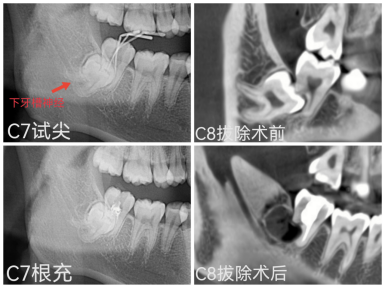

近日,一名患者因右下后牙咬合疼痛到深圳分院就诊。牙体牙髓科主任、主任医师梁燕接诊后,为其进行详细的病史采集、临床检查、CBCT影像检查,考虑为“C8近中低位阻生牙压迫致邻牙C7远中压根吸收,出现反复咬合疼痛”。

CBCT影像显示患者C7远中牙根吸收至根分叉处;C8为近中完全骨埋伏阻生牙,整颗牙齿完全在牙槽骨内,同时向前顶着邻牙C7的远中牙根致牙根吸收,且三颗牙根分叉、弯曲程度较大,牙根与右侧下颌管之间无骨质间隔(牙齿压迫下牙槽神经),因此拔除难度高,存在下牙槽神经损伤风险。

综合评估后,梁燕立即启动多学科联合诊疗(MDT),由口腔颌面外科、口腔正畸科、牙周黏膜科、口腔修复种植科MDT团队成员对患者病情进行详细充分地讨论,并综合患者及家属意愿,选择了“保留天然牙C7、拔除C8阻生牙”治疗方案。首先由口腔颌面外科主治医师陈友利完成C8阻生牙拔除手术,整个过程无痛,最大程度保护了邻牙C7牙周组织并保留了牙槽骨,规避了下牙槽神经损伤,减轻了患者疼痛、肿胀等术后反应。同期由牙体牙髓科主任医师梁燕、主治医师叶韵瑶对C7外吸收的远中牙根进行显微根尖手术于外吸收部位清创并切除根尖,应用生物陶瓷材料行远中根尖屏障术,封闭并完善根管治疗。最后由口腔修复种植科主治医师孟茂花完成C7冠修复治疗。

在MDT团队协作治疗下,成功为患者保留了天然牙C7。术后1周,患者来院复诊,术区伤口愈合良好,患者及家属对治疗效果满意。